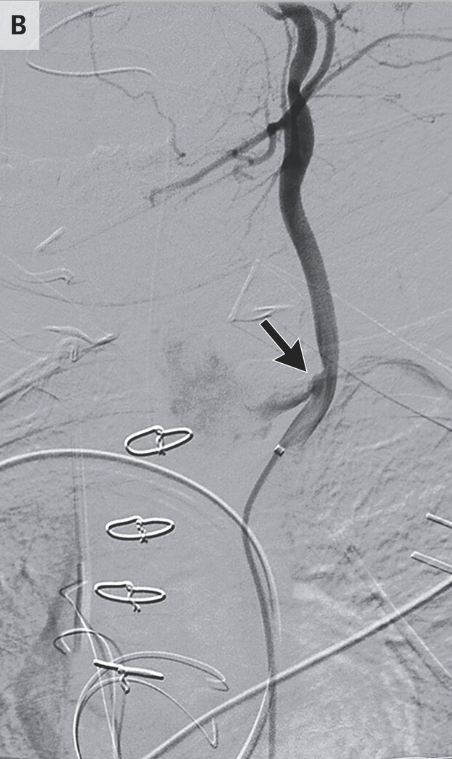

A previously healthy 11-month-old girl presented to the emergency department with a 2-week history of progressively worsening dysphagia and cough..A chest radiograph showed a foreign body with a “halo” or “double-ring” sign. Approximately 10 hours after endoscopic removal, “torrential hematemesis and hemorrhagic shock developed. During emergency surgical exploration, no source of bleeding was initially identified, but intraoperative angiography revealed a fistula between the esophagus, which was dilated, and the left common carotid artery (Panel B, arrow). The artery was ligated, and hemostasis was achieved.” The patient was discharged 32 days after admission without neurologic or functional deficits.